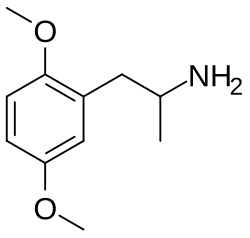

Activation of the 5-HT2A receptor is necessary for the effects of the "classic" psychedelics like LSD, psilocin and mescaline, which act as full or partial agonists at this receptor, and represent the three main classes of 5-HT2A agonists, the ergolines, tryptamines and phenethylamines, respectively. A very large family of derivatives from these three classes has been developed, and their structure-activity relationships have been extensively researched.[70][71] Agonists acting at 5-HT2A receptors located on the apical dendrites of pyramidal cells within regions of the prefrontal cortex are believed to mediate hallucinogenic activity. Some findings reveal that psychoactive effects of classic psychedelics are mediated by the receptor heterodimer 5-HT2A–mGlu2 and not by monomeric 5-HT2A receptors.[72][73][57] However, newer research suggests that 5HT2A and mGlu2 receptors do not physically associate with each other, so the former findings have questionable relevance.[74] Agonists enhance dopamine in PFC,[33] enhance memory and play an active role in attention and learning.[75][76]

Serotonin 5-HT2A receptor agonists include serotonergic psychedelics[77] and non-hallucinogenic agents.[78][79] Psychedelics have widely been encountered as recreational drug or drugs of misuse, with potential clinical consequences such as overdose, hospitalization, bad trips and worsened mental health, and rare adverse effects such as seizures, psychosis, and hallucinogen persisting perception disorder (HPPD).[80][81] On the other hand, psychedelics and non-hallucinogenic serotonin 5-HT2A receptor agonists are under development as novel treatments for psychiatric disorders like depression, anxiety, and addiction as well as other conditions like cluster headaches.[82][83][84][85][86] Both psychedelics and non-hallucinogenic serotonin 5-HT2A receptor agonists are claimed to act as psychoplastogens and this might be involved in their therapeutic effects.[85][87][88]